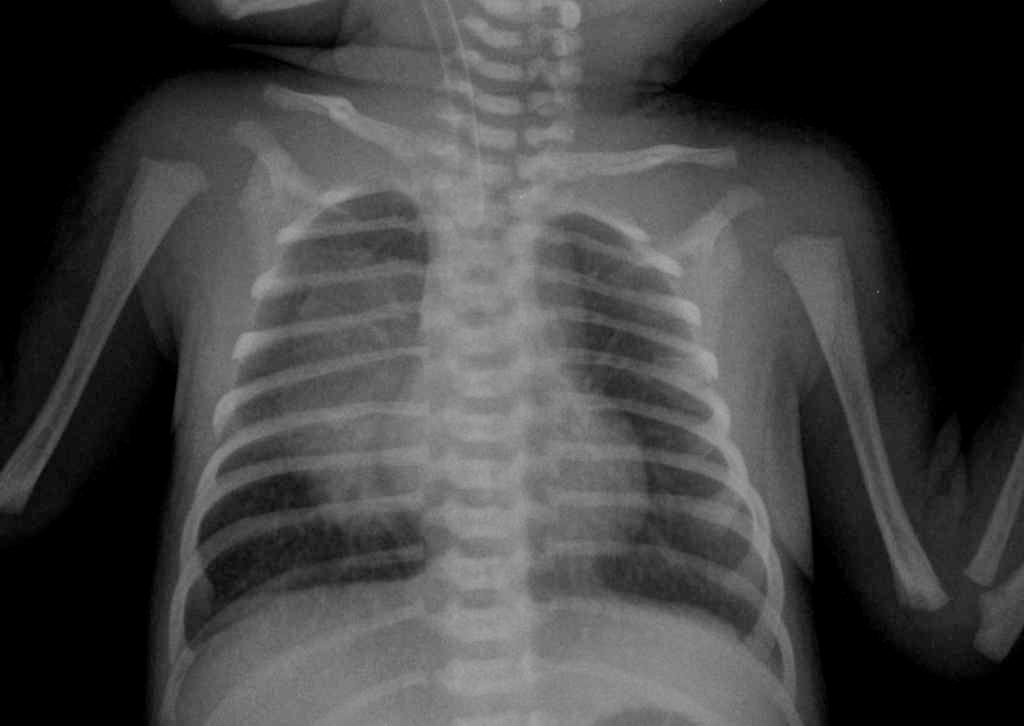

За счет инструментальных обследований можно точно определить поражение легких и уточнить, где оно локализовано. Особенно важен рентген легких новорожденного, при нем виды типичные признаки воспалительного процесса – уменьшение воздушности легких с усиление рисунка сосудов в начале пневмонии, а затем проявление воспалительных инфильтративных изменений с тенденцией их к слиянию. При недоношенности ребенка рентгенография не может точно дать сведения – пневмония ли это или болезнь гиалиновых мембран. Изменения очень похожи на фоне обеих патологий, поэтому необходимы анализы.